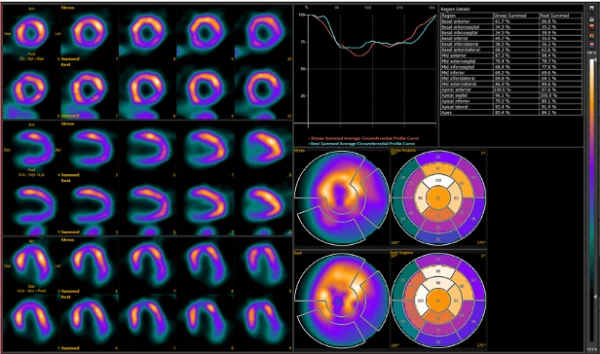

Это специализированное комбинированное устройство однофотонной эмиссионной компьютерной томографии/компьютерной томографии (ОФЭКТ/КТ) для осуществления различных томографических, кардиологических, онкологических и неврологических обследований. ОФЭКТ/КТ система ANYSCAN SC Mediso идеально подходит для 2D и 3D исследований и характеризуется большой производительностью и широким кругом решаемых проблем.

Для ПЭТ-визуализации в ОФЭКТ/КТ аппарате ANYSCAN SC Mediso применяется кольцевая конструкция с двумя прямоугольными детекторами Сцинтилляторы детекторов выполнены из кристаллов NaI размером 585х470 мм и толщиной 9,5; 12,5; 15,9 мм. Каждый детектор укомплектован 48 – 60-тью фотоэлектронными усилителями сигналов. Эта система обеспечивает трехмерное сканирование с высоким объемным разрешением картинки и позволяет получать множество плоскостей изображений в аксиальном поле обзора существенного размера. Все это уменьшает степень облучения или период сканирования вдвое. При этом ПЭТ-исследование осуществляется при постоянных перемещениях стола, что дает возможность задания необходимых параметров проведения процедуры и повышает качество получаемых результатов.

Совместное использование КТ и ОФЭКТ обеспечивает получение функциональной информации на молекулярном уровне и анатомической картины, с их последующим совмещением.